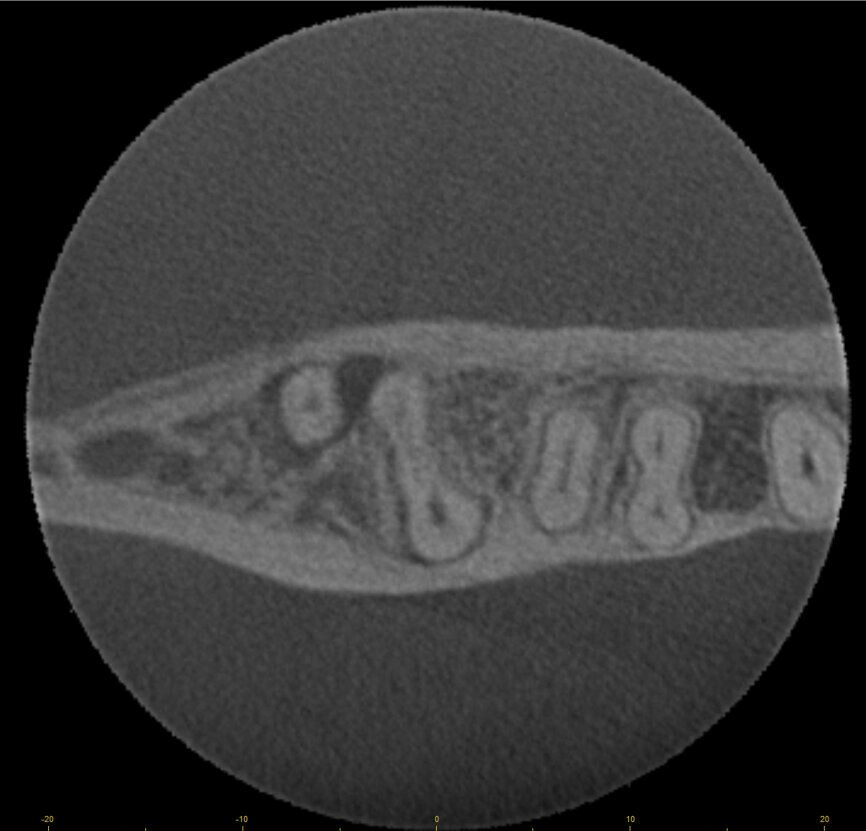

Fig. 17a: Case assisted with CBCT to determine anatomy pre-operatively. Note the multiple cross sections moving apically and the correlation to the 2-D view. Note also the conservative taper in relation to the root width. (Courtesy of Dr. Brett Gilbert)

Fig. 17b: Case assisted with CBCT to determine anatomy pre-operatively. Note the multiple cross sections moving apically and the correlation to the 2-D view. Note also the conservative taper in relation to the root width. (Courtesy of Dr. Brett Gilbert)

Fig. 17c: Case assisted with CBCT to determine anatomy pre-operatively. Note the multiple cross sections moving apically and the correlation to the 2-D view. Note also the conservative taper in relation to the root width. (Courtesy of Dr. Brett Gilbert)

Fig. 17d: Case assisted with CBCT to determine anatomy pre-operatively. Note the multiple cross sections moving apically and the correlation to the 2-D view. Note also the conservative taper in relation to the root width. (Courtesy of Dr. Brett Gilbert)

Fig. 17e: Case assisted with CBCT to determine anatomy pre-operatively. Note the multiple cross sections moving apically and the correlation to the 2-D view. Note also the conservative taper in relation to the root width. (Courtesy of Dr. Brett Gilbert)

Fig. 17f: Case assisted with CBCT to determine anatomy pre-operatively. Note the multiple cross sections moving apically and the correlation to the 2-D view. Note also the conservative taper in relation to the root width. (Courtesy of Dr. Brett Gilbert)

Managing complex anatomy is much simpler if the clinician has a pre-operative road map. The CBCT provides the roadmap and the surgical microscope the lens (literally) through which to visualize the result. Aside from a relaxed patient who is profoundly numb, being able to visualize anatomy by taking a pre-operative (and possibly intra-operative) CBCT and using a surgical microscope during treatment have no substitutes. They are the current “Gold Standard” in that 3-D imaging shows the clinician the true reality of a clinical situation as opposed to the suggestion gained from a 2-D radiograph. Proper interpretation of imaging prior to and/or during endodontic treatment goes a long way in taking the “guesswork” out of identifying canal location and other anatomical complexities as the procedure unfolds. In a 2014 study by El Fayad and Johnson, it was determined that when having a pre-operative CBCT as compared to 2-D radiographs alone, the treatment plan was modified 62 percent of the time. This is a huge game changer to think that the information learned from 3-D imaging changed the plan of treatment over six times out of 10 (Fig. 4).[2]